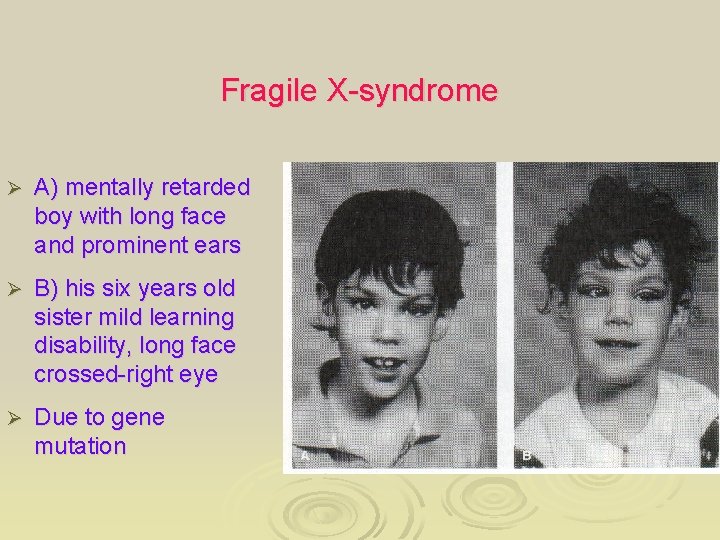

Fragile X-syndrome Ø A) mentally retarded boy with long face and prominent ears Ø B) his six years old sister mild learning disability, long face crossed-right eye Ø Due to gene mutation